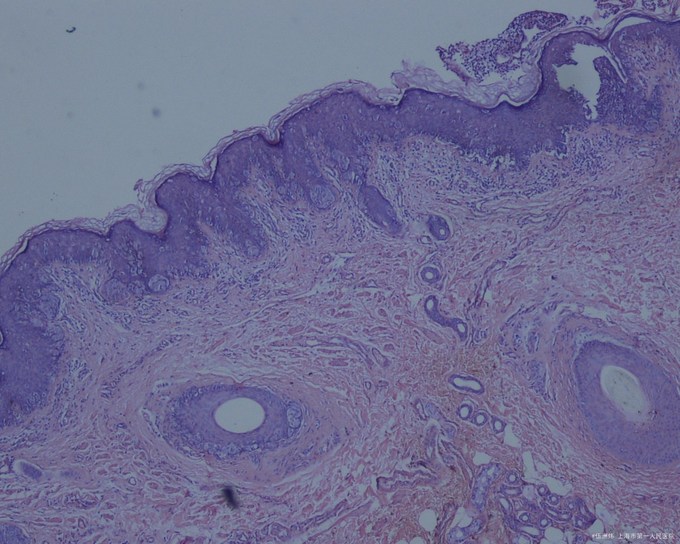

表皮内有不等量的Paget细胞,有时可见核被挤压在细胞的一边呈印戒状。在表皮附属器,特别是毛囊或外泌汗腺导管的上皮内也能见到Paget细胞,并能侵犯真皮,这与乳房Paget病不同。乳房外Paget病的Paget细胞含涎粘蛋白、耐淀粉酶和耐透明质酸酶,故对PAS、阿新蓝(pH 2.5)可呈阳性。免疫组化显示Paget细胞对癌胚抗原、顶泌汗腺上皮抗原均呈阳性,雌激素受体和孕激素受体阳性者较低,与乳房Paget病明显不同

原因 原发性乳房外Paget病的起源目前仍有争论,以往认为Paget细胞来源于汗腺癌沿导管上皮向表皮蔓延,但发现表皮及附属器的病变为多灶性起源,真皮内浸润来自表皮而非导管及腺体结构。免疫组化结果支持顶泌汗腺起源,推测它可能起源于顶泌汗腺导管开口部细胞,或是表皮内向顶泌汗腺分化的多潜能细胞。继发性乳房外Paget病的表皮病变常由深部直肠、子宫颈或膀胱癌扩展而来。 病理生理变化 表皮内有不等量的Paget细胞,有时可见核被挤压在细胞的一边呈印戒状。在表皮附属器,特别是毛囊或外泌汗腺导管的上皮内也能见到Paget细胞,并能侵犯真皮,这与乳房Paget病不同。乳房外Paget病的Paget细胞含涎粘蛋白、耐淀粉酶和耐透明质酸酶,故对PAS、阿新蓝(pH 2.5)可呈阳性。免疫组化显示Paget细胞对癌胚抗原、顶泌汗腺上皮抗原均呈阳性,雌激素受体和孕激素受体阳性者较低,与乳房Paget病明显不同。 症状体征 本病大多好发于男性,女性少见。常发生于50岁以上,病程缓慢,病期半年至十多年。其损害好发于顶泌汗腺分布部位,如阴囊、阴茎、大小阴唇和阴道,少数见于肛周、会阴或腋窝等处。大多为单发,少数多发,同时发生于两个部位者更少见,极少数患者可伴发乳房Paget病。乳房外Paget病可继发于腺癌的扩展,如从直肠到肛周区,从宫颈到女阴区,从膀胱到尿道、龟头或腹股沟区等。另一方面,长期在生殖器部位的乳房外Paget病可侵犯宫颈或泌尿道。损害如同乳房Paget病,呈界限清楚的红色斑片,大小不一,边缘狭窄,稍隆起,呈淡褐色,中央潮红、糜烂或渗出,上覆鳞屑或结痂,有时呈疣状、结节状和乳头瘤状,自觉有不同程度的瘙痒,少数有疼痛。 诊断检查 对50岁以上老年人发生在外生殖器部位或肛周长期不愈的湿疹样皮肤损害,特别是边缘明显者,应提高警惕,活检可以明确诊断。 治疗方案 首选手术切除,可用Mohs外科技术。若损害较大,累及腹股沟和肛周时,需作植皮术。继发性乳房外Paget病应对原发病作相应处理。复发病例可再次手术切除。